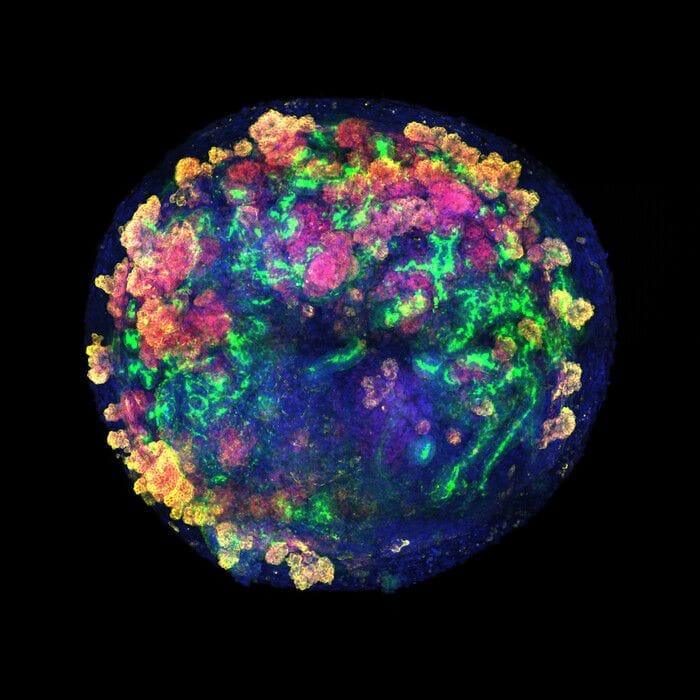

Una tecnica apre alla produzione di organoidi su larga scala

Una

nuova tecnica

promette di rendere

più facile

ottenere

organi

destinati ai

trapianti

a partire dagli

organoidi

, aggregati di cellule coltivati in laboratorio che riproducono le caratteristiche di tessuti e organi. Il primo esperimento è

pubblicato

sulla rivista Nature Biomedical Engineering dall'Istituto spagnolo di Bioingegneria della Catalogna e ha combinato in laboratorio organoidi umani di rene con reni di maiali. Quindi gli organi così ottenuti sono stati trasferiti nell'animale, dove sono risultati vitali.

Gli organoidi,

pur non essendo organi completi

, riescono a

riprodurre

molte delle principali

strutture e funzioni dell'organo

. Per questo motivo fin dall'inizio sono stati una

grande promessa

non solo per la ricerca si molte malattie e la sperimentazione di farmaci, ma per i trapianti. Tuttavia

farli crescere in laboratorio

attualmente richiede

molto tempo

.

I ricercatori coordinati da Núria Montserrat, attualmente ministro della Ricerca e dell'Università del Governo della Catalogna, hanno messo a punto un metodo basato su

tecniche di ingegneria genetica

che consente di ottenere

migliaia di organoidi renali in poco tempo

e con grande

precisione

.

I

primi esperimenti

sono stati condotti

combinando organoidi umani con reni di maiale

collegati a macchine 'di perfusione normotermica', dispositivi comunemente utilizzati per mantenere gli organi vitali e funzionali dopo il prelievo facendovi circolare un liquido arricchito di ossigeno e nutrienti a temperatura corporea. In questo modo, gli autori dello studio hanno potuto controllare l'organo in tempo reale e rilevare immediatamente eventuali segni di danno o rigetto.

A distanza di 48 ore dal trapianto, gli

organoidi umani

sono rimasti integrati nel tessuto suino, hanno

continuato a funzionare normalmente

e non hanno innescato alcuna risposta immunitaria significativa. Secondo i ricercatori, i risultati ottenuti permettono di immaginare un futuro nel quale gli organi destinati al trapianto possano essere preparati e riparati prima dell'intervento chirurgico.